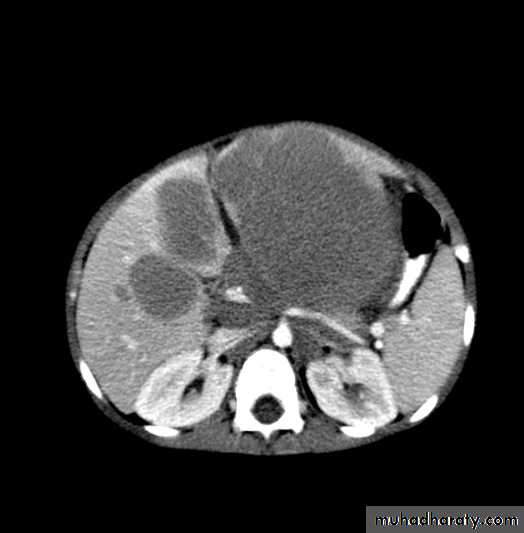

Neuroblastoma

Age90% < 5 y/o; 50% < 2 y/o

Location: any neural crest tissue

Adrenal

Paraspinal sympathetic tissue

Cervical, Thoracic, Pelvic

Often metastatic at diagnosis

Neuroblastoma: Signs and Symptoms

Abdominal mass

Often crosses midline